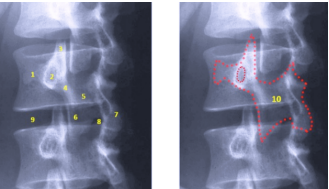

3. Oblíquas:

* Utilizada para visualizar os forames

intervertebrais (de conjugação)

1. Processo transverso

2. Pedículo

3. Processo articular superior

4. Pars interarticularis

5. Lâmina

6. Processo articular inferior

7. Processo espinhoso

8. Espaço discal